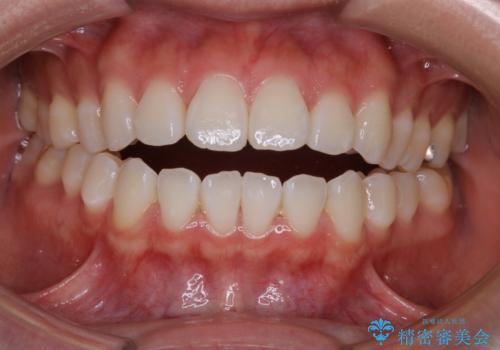

前歯で噛めない:オープンバイト(開咬)を非抜歯インビザラインで治療

- 上下の歯が噛んでいないことを気にしてご相談にいらした方です。

オープンバイトの方への治療は、通常抜歯を行いワイヤーによる矯正治療を行うことが多いですが、今回はインビザラインの特性を生かし、非抜歯にて綺麗な歯並びを作ることが出来ました。